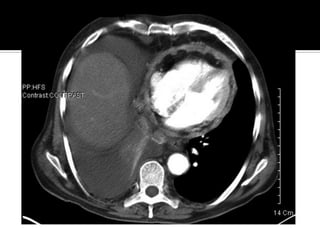

   CT provides detailed images of the pericardium and is especially

helpful in detecting even minute amounts of pericardial calcification.

Its major disadvantage is the frequent need for iodinated contrast

medium administration to best display findings of pericardial

pathology. The thickness of the normal pericardium measured by CT

is less than 2 mm.

CT scan performed during an infusion of contrast material shows enhancement of the soft-tissue-

density pericardium (arrowheads), which is up to 6 mm thick.